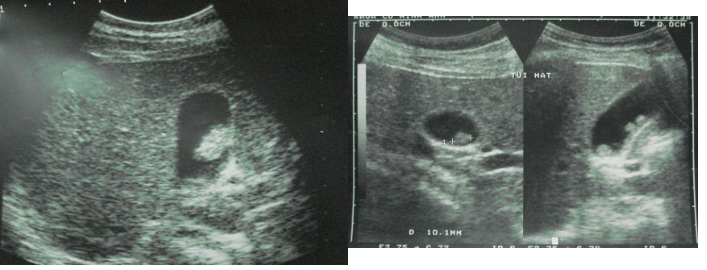

Polyp túi mật là những thương tổn dạng u hoặc giả u nhô lên trên bề mặt niêm mạc của túi mật. Bệnh này gần đây hay gặp hơn, chiếm từ 5-15% trong số bệnh nhân mổ cắt túi mật. Polyp túi mật đại đa số là lành tính (trên 90%) và có tỷ lệ nhỏ (<10%) là ác tính. Polyp túi mật có thể gây viêm túi mật, tạo điều kiện gây sỏi mật và có thể tiến triển ung thư hoá (nhất là ở các BN lớn tuổi, polyp đơn độc và có kích thước lớn).

Triệu chứng bệnh có thể thấy đau tức nhẹ vùng dưới gan, đầy bụng, khó tiêu và chủ yếu phát hiện tình cờ qua siêu âm hoặc chụp cắt lớp vi tính. Phẫu thuật cắt túi mật đặt ra khi có một trong số các yếu tố sau: polyp có triệu chứng, có nhiều polyp hoặc kích thước của polyp lớn (trên 10mm) và các BN trên 50 tuổi.

Với những trường hợp polyp túi mật có biến chứng viêm túi mật cấp hoặc ung thư hoá cần được phẫu thuật cắt bỏ túi mật. Các trường hợp polyp túi mật không có triệu chứng cần được theo dõi tiến triển trong thời gian từ 3-6 tháng, nếu thấy polyp to nhanh hoặc thành túi mật dày lên thì nên đến mổ cắt bỏ túi mật. Mổ nội soi cắt túi mật là tiêu chuẩn vàng và mang lại nhiều ưu điểm như nhanh hồi phục sau mổ, ít đau, ít biến chứng và tính thẩm mỹ cao.